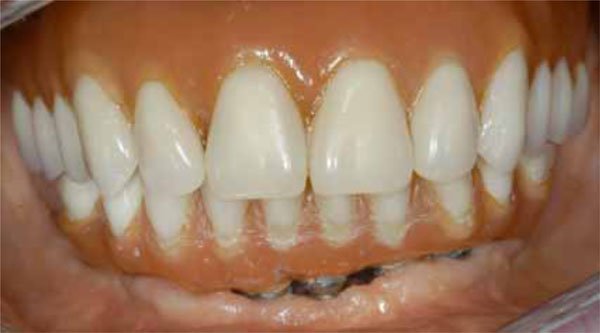

Fig. (10).

Buccal view of the final prosthesis in situ.

Fig. (11).

Occlusal view of the final prosthesis in situ.

After a healing period of 6 months, all implants achieved successful integration. Clinical evaluation showed no signs of complications and the panoramic radiographs showed no evidence of peri-implant radiolucency. A partial thickness flap was performed to uncover the implants and the healing abutments were placed (Fig. 9). In partially edentulous patients, temporary crowns were placed after a 3-week healing period and were left in situ for 6 months in order to modify and condition soft tissue contour and shape. All cases were restored with a fixed restoration to replace the missing teeth (Figs. 10 and 11).